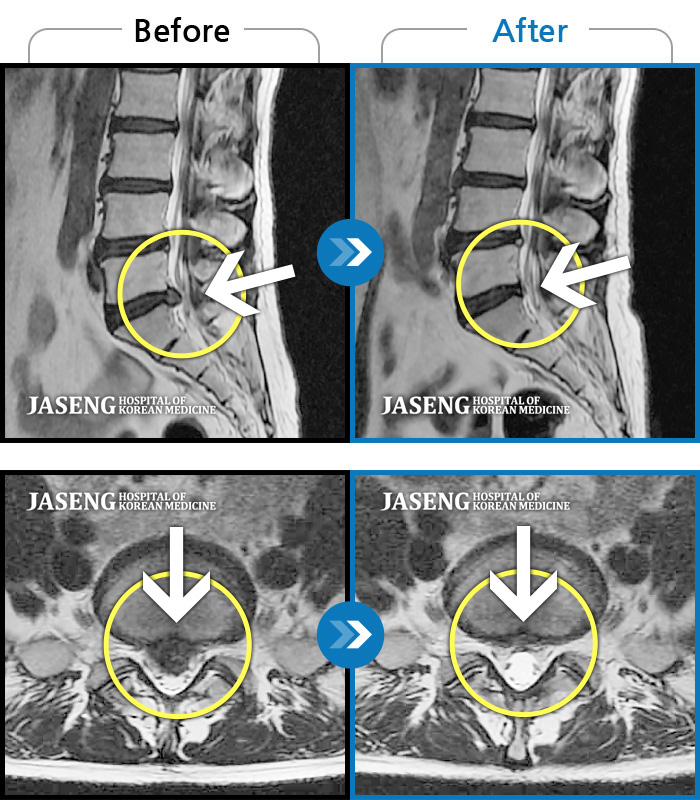

MRI사진에서 좋아지고 있다는 말씀에 넘 기뻤습니다^_^